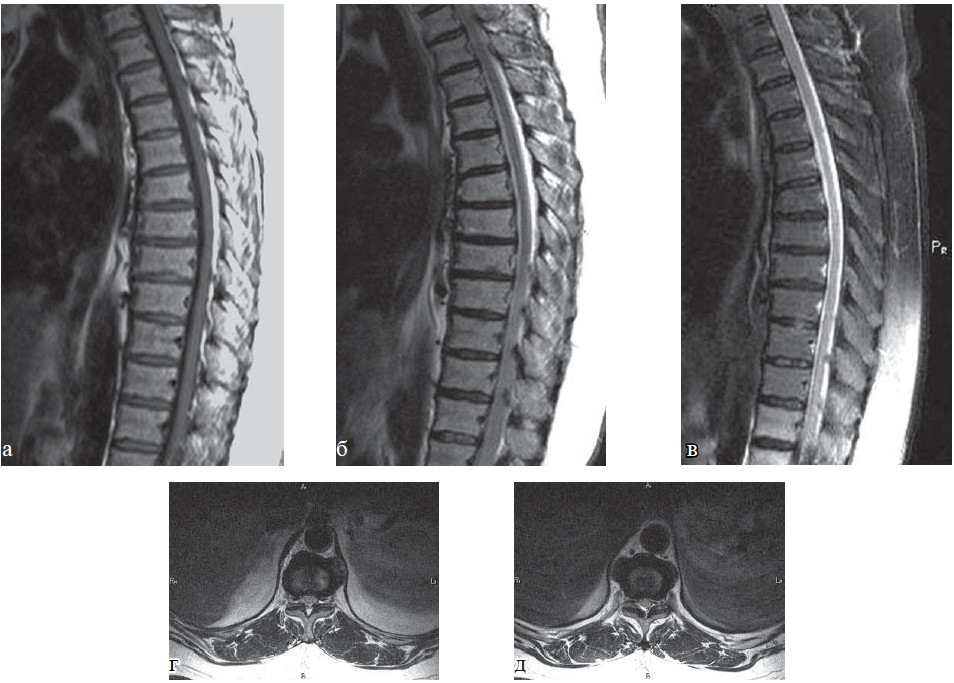

Во 2-ю группу отнесены 493 пациента, у которых были выявлены умеренный остеохондроз позвоночника (II-III стадия), дискоз II стадии с дегенерацией межпозвонкового диска и его пролапсом до 3-7 мм, с умеренными явлениями спондилоартроза, без нарушения или минимальными изменениями плотности и структуры кости (остеопения), спондилолистез I степени с признаками дегенеративно суженного позвоночного канала либо наличием нестабильности при функциональных пробах (рис. 5-6).

Рис. 5. КТ грудного отдела позвоночника, пациент Д., 43 года: а, б — аксиальная плоскость; в — сагиттальная; г — фронтальная; д — режим объёмного рендеринга. Определяется остеохондроз грудного отдела позвоночника II степени, остеоартроз реберно-позвонковых сочленений, гемангиомы тел позвонков Th5, Th11, L1 (стрелки)

Рис. 6. КТ поясничного отдела позвоночника, больная Н., 58 лет: а—в — аксиальная плоскость; г—е —сагиттальная плоскость. Определяется остеохондроз поясничного отдела позвоночника II степени, протрузия межпозвонкового диска L3—4, грыжа межпозвонкового диска L4—5, спондилоартроз, спондилолиз дуги позвонка L5, задний спондилолистез позвонка L4 I степени, передний спондилолизный спондилолистез позвонка L5 I степени.